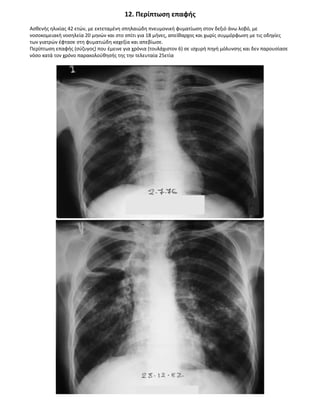

12. Περίπωση επαφής 574